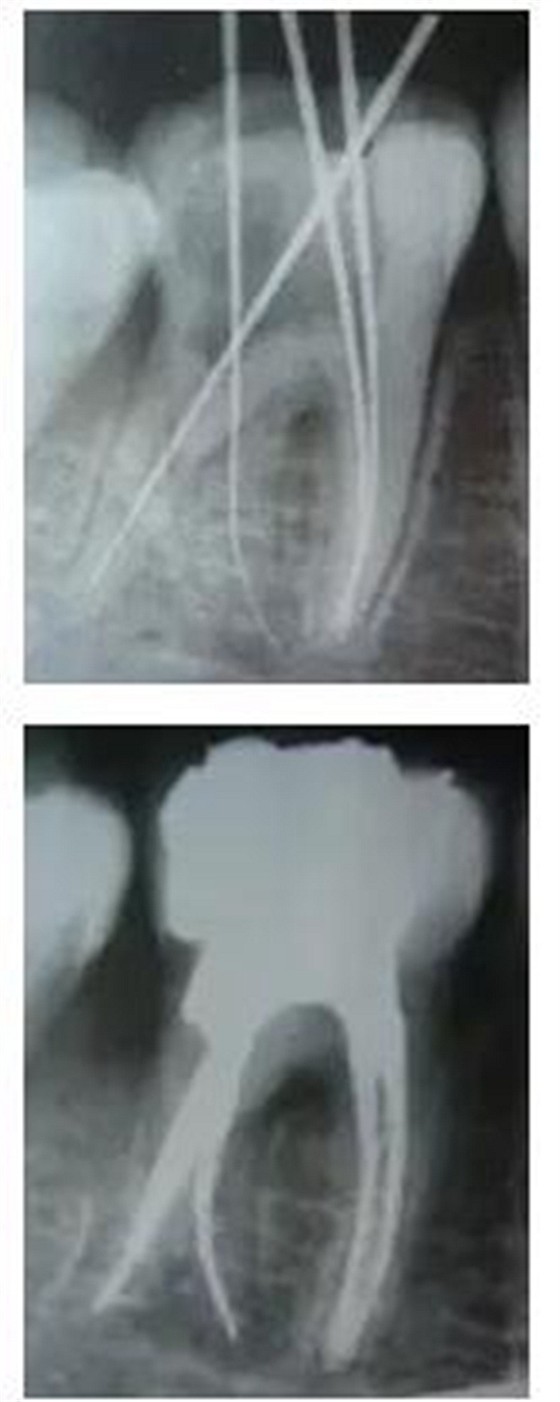

最后來玩一個根管治療質(zhì)量的評估——下圖是武大彭彬教授的一個病例,仔細(xì)觀察可以挑出一點問題,但問題事出有因!看看你的“眼力”如何——問題在那里?教授的專業(yè)水平是不用懷疑的,那么事出的原因可能是什么?

再次分享根管治療的點滴見解! 再次分享根管治療的點滴見解!

問題答案:這個病例的問題主要反應(yīng)在開髓的洞形修整,注意觀察該牙X-RAY的左側(cè)洞壁,如果常規(guī)情況制備成這樣是由于裂鉆破壞了洞壁和洞底所形成的臺階。如果評估根管治療的質(zhì)量那是要扣分的!但這個病例仔細(xì)觀察洞壁形態(tài)就可以看出:該病例屬于再治療的病例,因此還是屬于一個理想的病例。